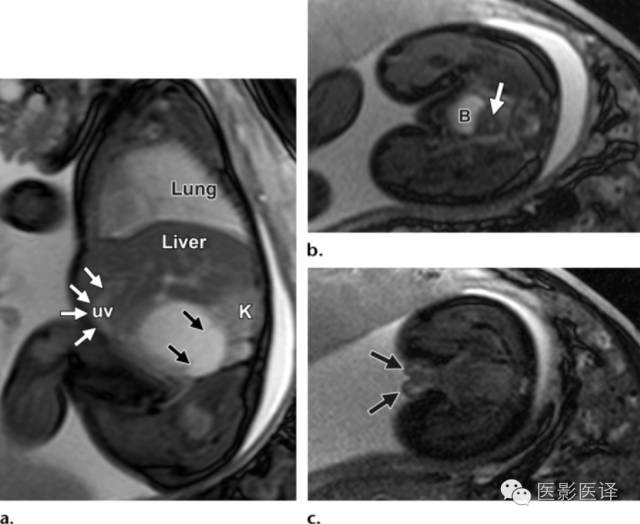

因母亲体型、胎儿位置或羊水过少而声学评价受限的病例,MR成像就很有帮助了(图8)。MR成像也可用于确认女性生殖器官和正常胃肠道及泌尿生殖道,这些是诊断胎儿卵巢囊肿所必须的。快速T2WIMR成像序列有助于显示解剖,TIWI MR成像显示胎粪为高信号,这能显示结肠走向并确认直肠。

图8MR图像可清晰显示胎儿解剖。(a)稳态进动MR图像矢状位显示一囊肿内伴多发分隔(黑箭),该囊肿位于肝脏下缘、肾脏(K)前缘。可见脐静脉(uv;白箭)进入肝左叶。(b,c)稳态进动MR图像横断位显示胎儿子宫(图b中箭头所示)位于膀胱(B)后方,提示女性内生殖器,阴唇(图c中箭头所示),提示女性外生殖器。证实了女性生殖器存在也就可以支持卵巢囊肿的诊断;若显示为男性生殖器则可以将卵巢囊肿从鉴别诊断中排除。